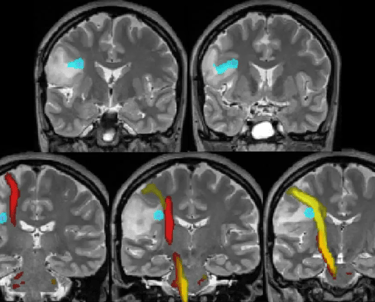

Published in the journal Nature by psychiatrists at Weill Cornell University. Functional magnetic resonance imaging (fMRI) scanners were used to compare the brain activities of clinically depressed and healthy people.